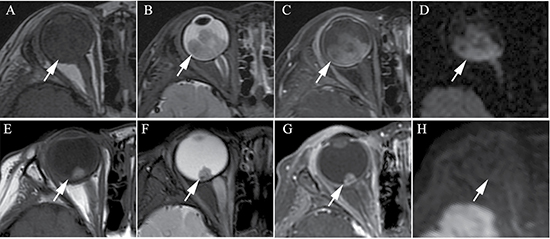

Figure 1: Clinically diagnosed retinoblastoma in a 24-month old male (patient 1). (A–H) An orbital mass is shown at the right globe with the tumor totally or partially covering the optic disk before intra-arterial chemotherapy (IAC), which demonstrates a slightly higher signal intensity than the ocular fluid as observed in axial T1-weighted magnetic resonance imaging (MRI) (A), low signal intensity (arrow) in the axial T2-weighted MRI (B) and moderate enhancement of the retinoblastoma (arrow) in the axial contrast-enhanced, T1-weighted, fat-saturated MRI (C). The axial DWI (D) shows restricted diffusion (arrow) in the tumor, a finding indicative of high tumor cellularity. (E–H) The axial T2-weighted MRI (F) shows that the size of the tumor is diminished after treatment with IAC and demonstrates a low signal intensity of the residual tumor foci partially covering the optic disk (arrow). The axial contrast-enhanced T1-weighted, fat-saturated MRI (G) shows non-enhancement of the residual tumor foci with comparison to the high signal intensity found in the T1-weighted MRI (E). The axial DWI (H) shows the low signal intensity of the residual tumor foci (arrow).

The size of the tumors was obviously diminished after IAC in all 60 eyes, including the mean maximum diameter (t = 19.15; P < 0.001), the mean thickness (t = 18.49; P < 0.001), and the maximum cross-sectional area (t = 21.35; P < 0.001) (Figure 1 and Figure 2). Both group D and group E showed a significant difference in tumor size after IAC. There was no significant difference between the patients of group D and group E in the tumor size before or after treatment.

Among the 60 eyes, compared to pretreatment, 51 tumors with moderate enhancement decreased to non-enhancement (Figure 1 and Figure 2) (n = 46; 90.2%) or slight enhancement (n = 5; 9.8%), and the other nine tumors changed from slight enhancement to non-enhancement (n = 9; 100%). Nodular enhancement of postlaminar optic nerves observed in six (10%) affected eyes before IAC disappeared after IAC (Figure 3).